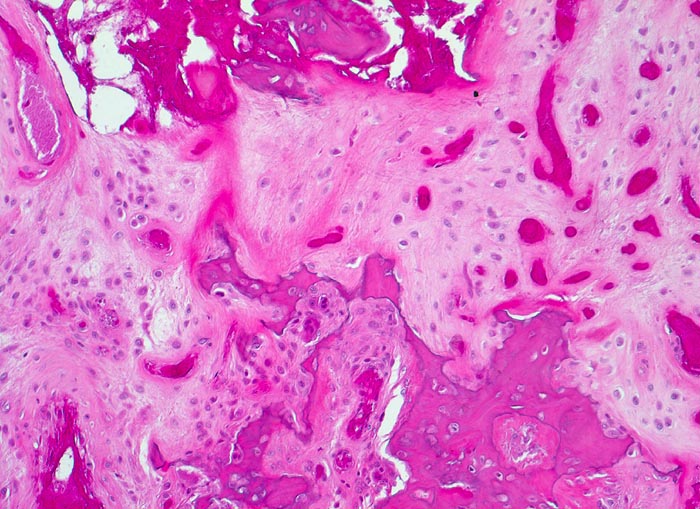

PathoPic – image database / PathoPic ID 4783 - aseptische Femurkopfnekrose

aseptische Femurkopfnekrose

vaskulär / Durchblutungsstörung

Knochen, Femurkopf

Nekrosezone: kleine avitale Knochenfragmente liegen eingebettet in neugebildete fasrige extrazelluläre Matrix. Der ortsständige Knochen wird von Osteoklasten abgeräumt.

Histologie

100